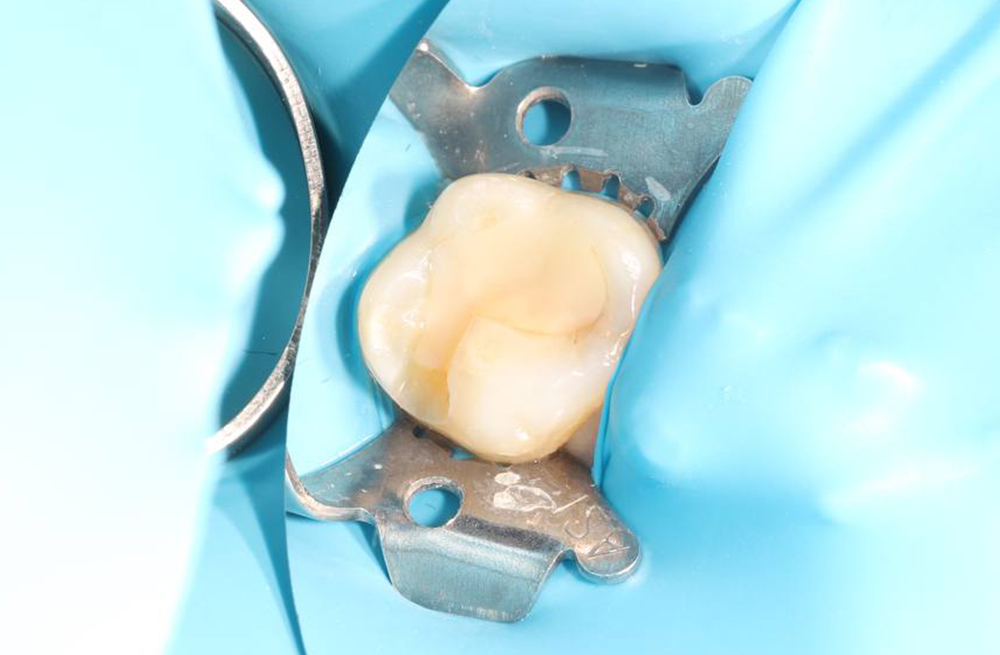

Композитная реставрация жевательных зубов при кариозном поражении

Устранение кариозного поражения зуба с применением коффердама и композитной реставрации